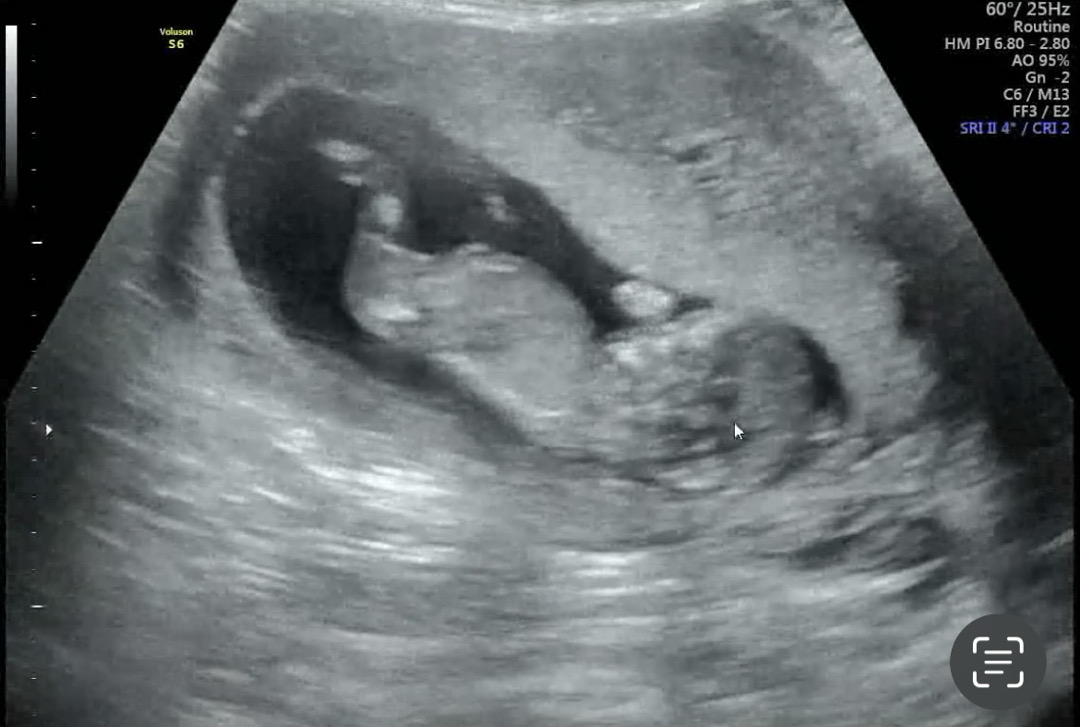

12주 2일이구 초음파가 넘 흐린듯 하고 아기가 너무 움직인데욤 ㅋㅋㅋㅋ ㅠㅠㅠ 한번 유추라도 해보고 싶어서 재미삼아 올려욤 다같이 봐주세용😆💛 목투명대랑 코뼈유무 패스라서 일차 안심하고 왔습니다 오늘은 기분 좋게 맛있는거 먹을려규욤 😆